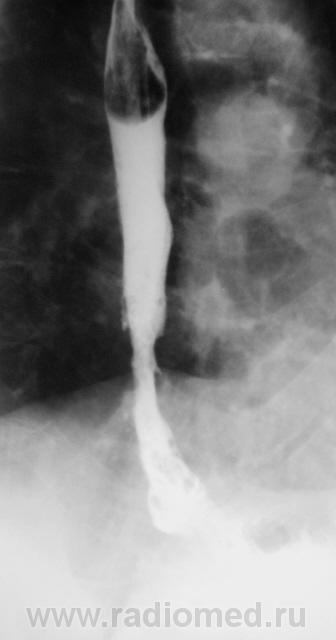

Пациент направлен на рентгенологическое исследование пищевода после ФГДС с диагнозом - "Пищевод Барретта".

Пациент первично был направлен в онкологический диспансер (областной). От туда он был направлен по месту жительства для производства ФГДС, которая и была проведена, был выставлен выше указанный диагноз.

После ФГДС, врач эндоскопист рекомендовал провести рентгеновское исследование пищевода.

Расценивать данное состояние как пищевод Баретта без биопсии, тем более участок неравномерного сужения в ретрокардиальном сегменте с ТАКИМИ контурами - смело...., как мне кажется...но все таки...

1. Пищеводно-желудочный переход отсутствует - это одно из подтверждений пищевода Баррета.

2. Наблюдаемое сужение может быть следствием эзофагеального стеноза в зоне трансформации эпителия - это тоже подтверждение пищевода Баретта, но как без биопсии дифференцировать с инфильтративной формой рака....

3. Нишеподобное выпячивание по левой стенке может быть пептической язвой - это тоже характерно для пищевода Баретта....

Циркулярное сужение в н/3 + отсутствие складок на уровне поражения + формирующееся престенотическое расширение = рак н/3 пищевода. Ну, а Барреты? А Барреты потом...